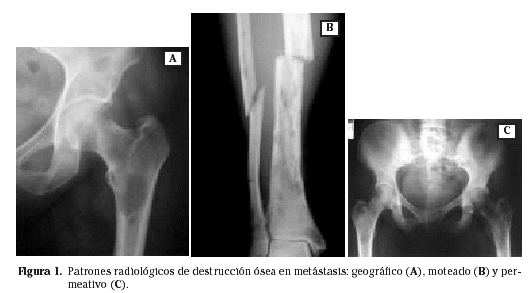

Se han descrito tres tipos de lesiones radiológicas según la forma y características de la destrucción ósea (Fig. 1). La primera asemeja una imagen geográfica, con una osteolisis grande, solitaria, con buena definición de márgenes, que puede confundir en ocasiones con una lesión benigna. La segunda es una imagen moteada, con múltiples pequeñas áreas líticas afectando a hueso esponjoso y cortical, con bordes poco definidos o indefinidos, dando ya un aspecto claro de malignidad. La tercera es una imagen permeativa de múltiples pequeñas áreas osteolíticas de 1 mm de tamaño o menores que se unen para dar un aspecto de destrucción corticomedular franco, límites indefinibles y apariencia de gran agresividad 6,14.